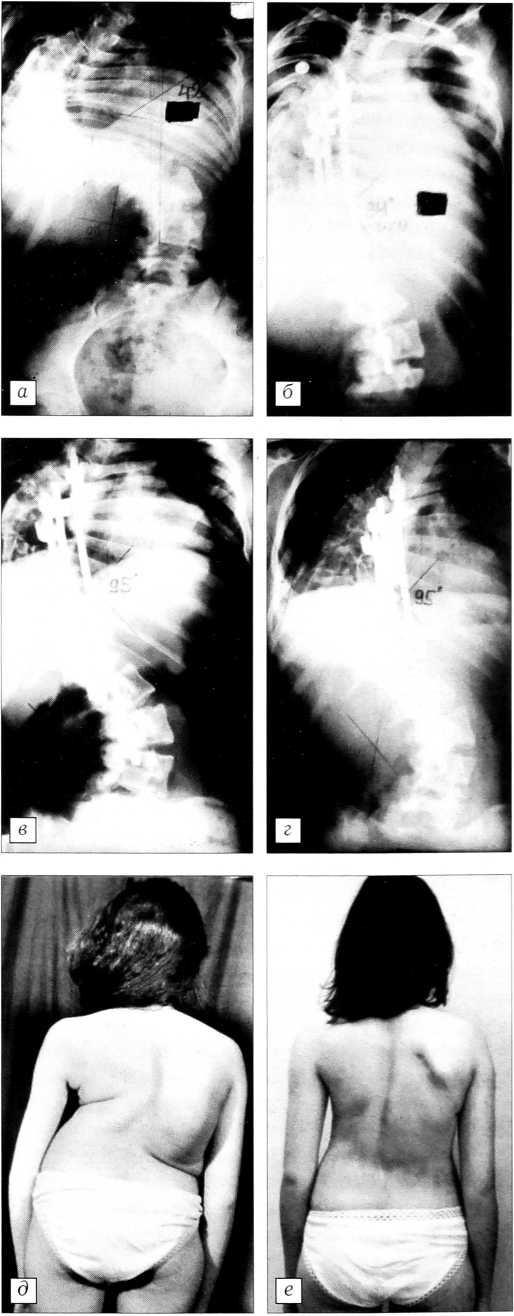

У 7 больных рассматриваемой группы изначально имелось и увеличение кифоза в грудном отделе — в среднем 90°. Уменьшить кифоз до 60° удалось у 5 пациентов, у 2 больных с изначальным кифозом 70° достигнута коррекция на 30°. Поясничный лордоз в пределах физиологического сохранен практически у всех больных. У 6 пациентов деформация была декомпенсированной. У 4 из них удалось полностью устранить декомпенсацию, а у 2 перевести ее в субкомпенсацию (рис. 2).

Рис. 2. Больная В. 21 года. а — рентгенограммы до операции: декомпенсированная деформация; б — после операции: коррекция общего угла 48° (50% от полной коррекции), декомпенсация устранена; в — внешний вид больной до операции, г — после операции.

Нами оба этапа хирургического лечения выполнялись одномоментно. В дооперационном периоде мы оценивали мобильность деформации, производя рентгенографию позвоночника в положении больного стоя в прямой проекции и лежа с вытяжением за петлю Глиссона и тазовый пояс грузом, составляющим 70% от массы тела пациента. При этом, несмотря на то что величина деформации у наших больных была значительной, при рентгенографии с вытяжением мы отметили уменьшение ее в среднем на 27,8°. Дополнительная мобилизация позвоночника (дискэктомия на нескольких уровнях) позволила увеличить мобильность еще на 20°. Полученная коррекция общего угла составила в среднем 45,4% от полной коррекции, а центрального угла — 45,1% (рис. 4). N. Tokunaga и соавт. [23] приводят результаты лечения группы больных сколиозом (21 человек), сопоставимой по величине деформации с нашей группой. Авторы производили деканцеляцию тел позвонков на вершине деформации, галофеморальную тракцию и затем через 3-4 нед дорсальную коррекцию. Полученная коррекция общего угла составила у них 46% , центрального угла (вершины деформации) — 49%. Как видно, разница между нашими данными и данным N. Tokunaga и соавт. незначительна, и это несмотря на то, что они применяли более активную мобилизацию на вершине деформации (деканцеляция) и галофеморальную тракцию.

Рис. 4. Больная В. 16 лет. а — рентгенограмма до операции, б — после операции (дискэктомия с Т4 по Т11, коррекция деформации системой CD): коррекция общего угла 52° (38% от полной коррекции); в — рентгенограмма через 1 год, г — через 2 года после операции: потери коррекции общего угла нет, противодуги — 10°; д — внешний вид больной до операции, е — после операции.

При использовании инструментария Харрингтона и Люке у наших больных была достигнута несколько меньшая коррекция (38,3°), а спустя 2,5 года после операции потеря коррекции общего угла составила у них 10-12°. При применении инструментария CD потеря коррекции до 10° отмечена у 2 больных. Это были пациенты с большим потенциалом роста (тест Риссера на момент операции 0-1, вторичные половые признаки отсутствовали). Потеря коррекции противодуги наблюдалась несколько чаще — у 5 больных. Мы связываем это с тем, что противодуга фиксировалась у них лишь частично.